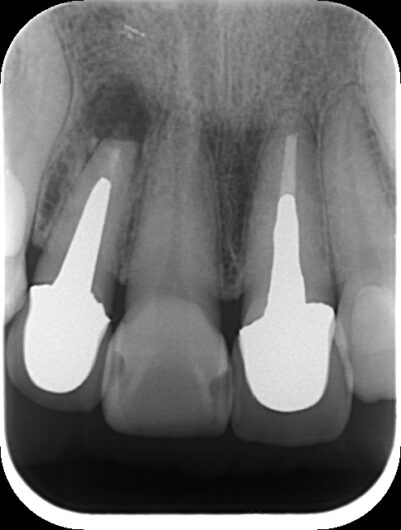

初診時レントゲン・CT

膿が大きく認められました。